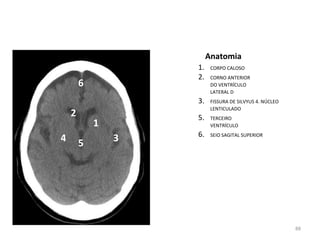

Anatomia

1. CORPO CALOSO

2. CORNO ANTERIOR

DO VENTRÍCULO

LATERAL D

3. FISSURA DE SILVYUS 4. NÚCLEO

LENTICULADO

5. TERCEIRO

VENTRÍCULO

6. SEIO SAGITAL SUPERIOR